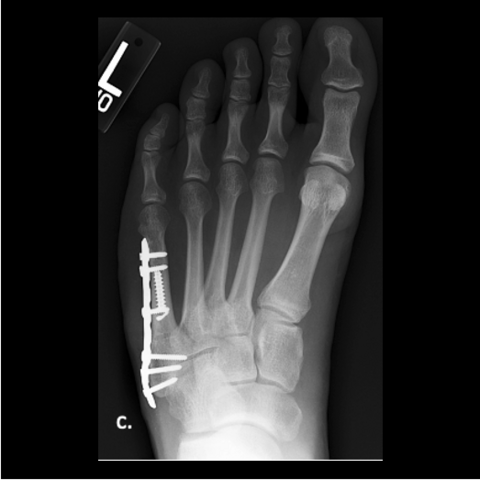

Figure 4a

Figure 4a. A 24-year-old male soldier refractured 1 year after his original surgery. He had returned to Airborne status with at least 15 jumps since his original surgery, with no issues running. Here is the 24-year-old soldier’s foot 6 months post-surgery.

Figure 4b

Figure 4b. Here is the 24-year-old soldier’s foot 6 months post-surgery.

-

Figure 4c

Figure 4c. Here is the 24-year-old soldier’s foot 6 months post-surgery.